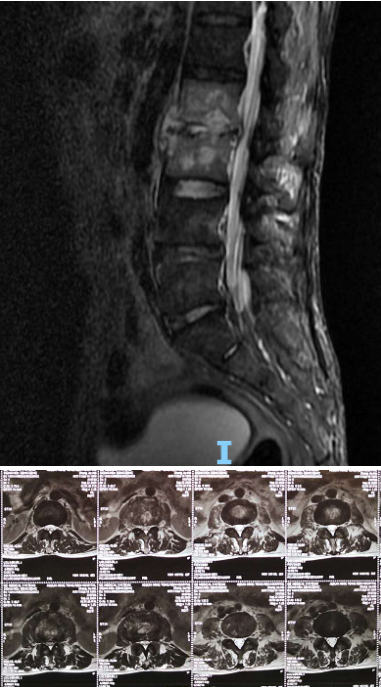

术前腰椎MRI

患者张某某,男性,51岁,云南曲靖人。患者自诉1月前不明显诱因出现腰部疼痛,并且进行性加重,活动后明显加重,在当地县中医院就诊行针灸等治疗无好转,后到县医院行腰椎MRI等检查显示:腰2、3椎体及椎旁软组织异常信号,结核、其他感染病变不能排除。后为进一步诊治,到昆明某医院就诊并住院治疗,行“L3椎体穿刺活检术”,病理报告提示:慢性炎性细胞浸润,诊断为:腰2、 3椎体感染,予静脉应用抗生素抗感染等治疗一周,出院后继续在当地继续抗感染治疗。

患者出院后感腰部疼痛持续加重,到杏吧原创 门诊就诊,以“腰椎感染”收住入院。患者发病后腰椎CT及MRI均提示腰2-3椎间隙变窄,椎板破坏,综合以上资料诊断”腰椎结核”。入院后经口服四联抗结核药物治疗3周,患者自觉腰部疼痛减轻,午后无发热及盗汗后,在全麻下行颈后路病灶清除、椎间植骨、椎弓根钉棒系统内固定术。手术顺利,术后继续抗结核治疗。患者恢复顺利,术后1周下床活动,无特殊不适。术后2周拆线、出院,院外继续口服抗结核药物治疗,定期门诊复查。